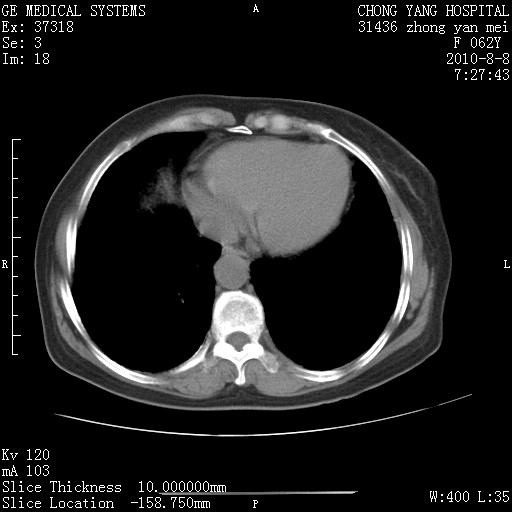

标题: CT28269:F62Y咳嗽胸痛数月。 [打印本页]

标题: CT28269:F62Y咳嗽胸痛数月。

1.肺间质纤维化.

2.纵隔淋巴结肿大。

3.迷走右锁骨下动脉。

两肺间质改变,纵隔淋巴结肿大,需要考虑结节病的可能。